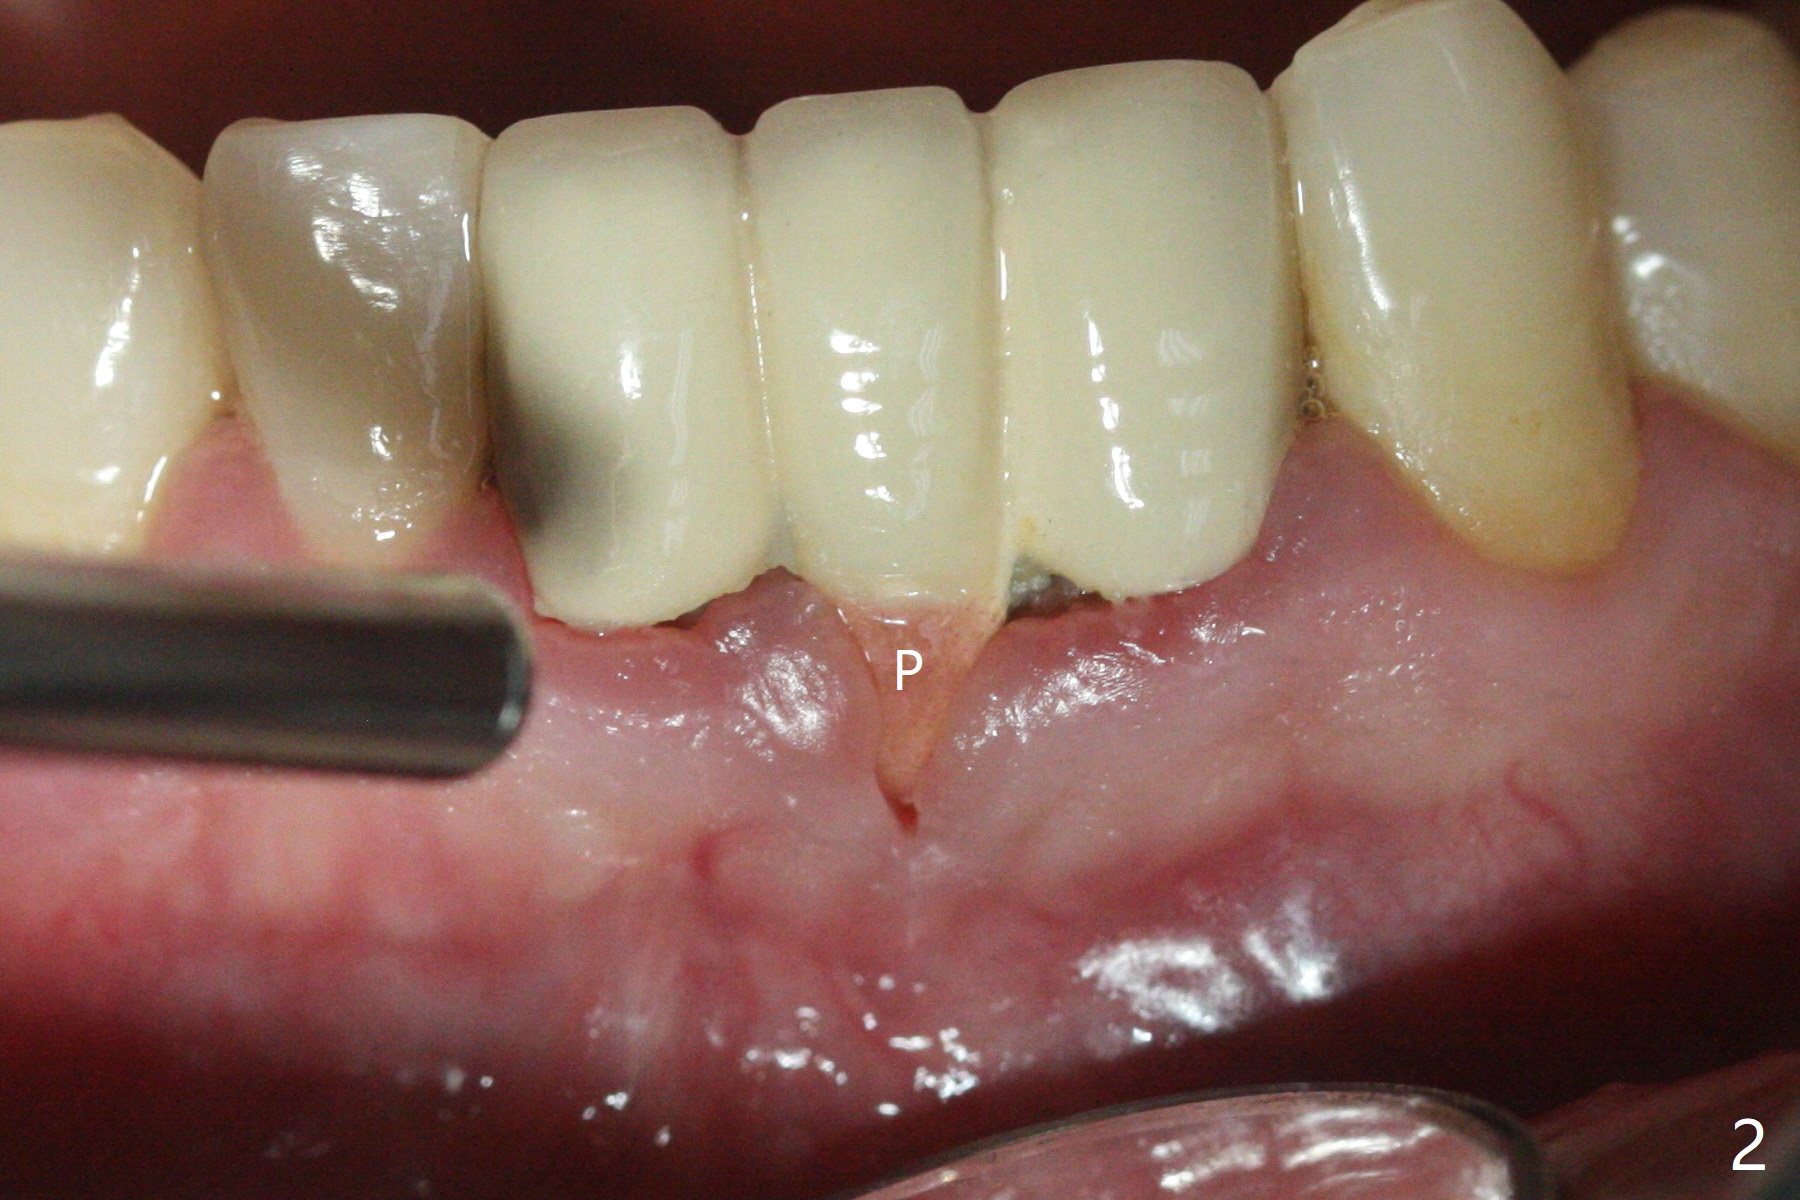

A 38-year-old man has gingival erythema and edema associated with #23-25 bridge (Fig.1). The most abnormal finding is the long pink porcelain at the pontic (Fig.2, 3: P). After taking Alginate for future provisional, the bridge is removed. The edentulous ridge must be atrophic, as shown in low density (Fig.3: *). A 2.0 mm 1-piece implant is proper for the site, as will be shown by CT. In fact 2.5 mm one is proper (Fig.4). The gingival erythema reduces significantly post bridge removal, SRP and water pik. After incision, surgical handpiece and diamond round bur are used to flatten the ridge until 4 mm.